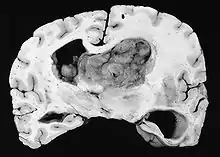

Generalmente, el SEGA se muestra como una lesión nodular bien circunscrita en relación con la masa cerebral adyacente. En la literatura son muy raros los casos de propagación (por ejemplo, a la médula espinal) y de malignización.[2] Este tumor es claramente visible en la resonancia magnética, donde presenta realce tras la aplicación del medio de contraste.

Los astrocitomas subependimarios de células gigantes se dan sobre todo en niños y adultos jóvenes. Dado que el tumor se desarrolla preferentemente en las paredes del sistema ventricular en la proximidad del foramen de Monro, el flujo de salida del líquido cefalorraquídeo suele verse alterado a medida que el tumor crece. El tumor suele crecer muy lentamente y se muestra en las imágenes de RM y TC como una masa circunscrita con calcificaciones y signos de sangrado antiguo. En algunos casos, el SEGA es la manifestación inicial de la esclerosis tuberosa y, por lo tanto, es un criterio diagnóstico importante. Sin embargo, sólo entre el 5 y el 20% de todos los pacientes con esclerosis tuberosa desarrollan SEGA.[3]

Histológicamente, son características de la lesión las células gigantes astrocíticas; sin embargo, la morfología de las células tumorales puede variar desde células poligonales con citoplasma vítreo y núcleos ganglioides hasta células fusiformes en una matriz fibrilar. Las células tumorales muestran una expresión variable de GFAP, S-100, sinaptofisina y neurofilamentos.